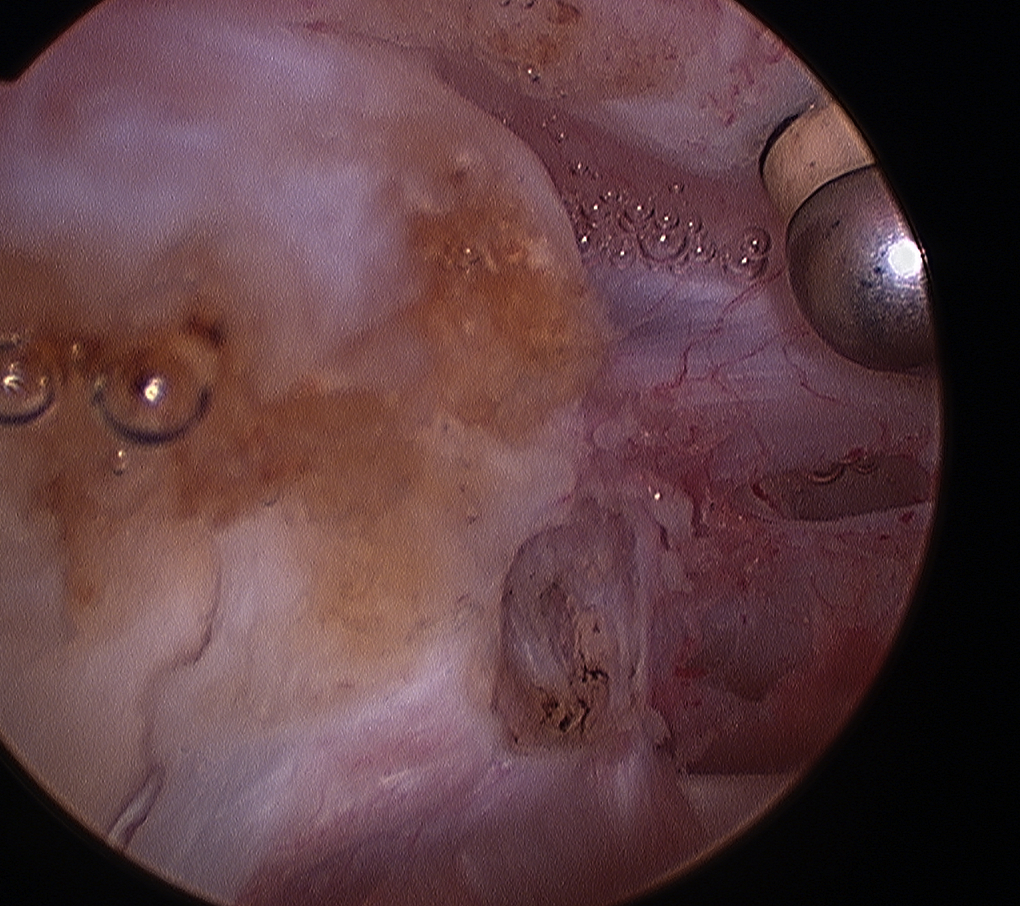

Normal

Tendonopathy

Medial subluxation of LHB